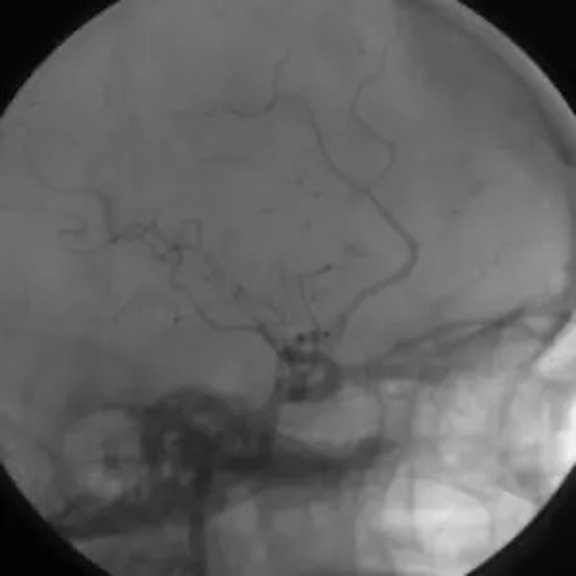

Einsatz genetischer Algorithmen zur Erstellung realer, farbkodierter 3D-Modelle zur gleichzeitigen Darstellung von Hämodynamik und Morphologie in zerebralen arterio-venösen Malformationen (2014 – 2016)